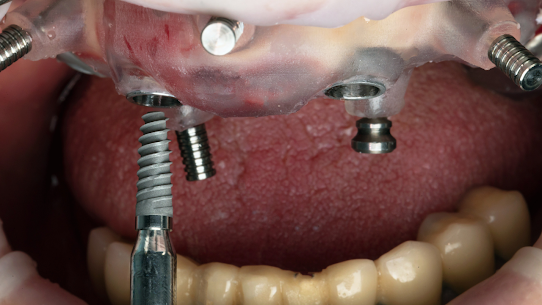

Réhabilitation complète (All-on-4 / All-on-6)

guides chirurgicaux à agdal, Rabat

Qu'est-ce qu'un guide chirurgical pour les implants dentaires - et pourquoi est-ce important ?

Lors de la pose d’implants dentaires, la précision est essentielle. C’est pourquoi nous utilisons un guide chirurgical sur mesure – conçu à partir d’un scan numérique de votre bouche – pour nous assurer que l’implant est placé à l’angle, à la profondeur et à la position parfaits.

✔️ Une chirurgie plus rapide et plus sûre

✔️ Placement plus précis de l’implant

✔️ Moins de risques, moins de douleurs, guérison plus rapide

✔️ Des résultats d’apparence naturelle

✔️ Implants plus durables